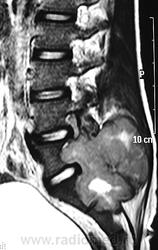

ГМ. СМ. Гигантоклеточная опухоль. +

Гигантоклеточная опухоль рояснично-крестцовой области.